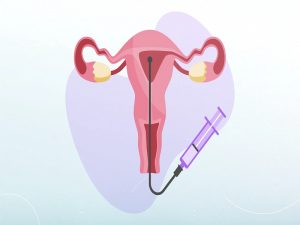

تلقیح داخل رحمی IUI (آی یو آی)

تلقیح داخل رحمی (IUI) کم تهاجمی ترین روش های کمک